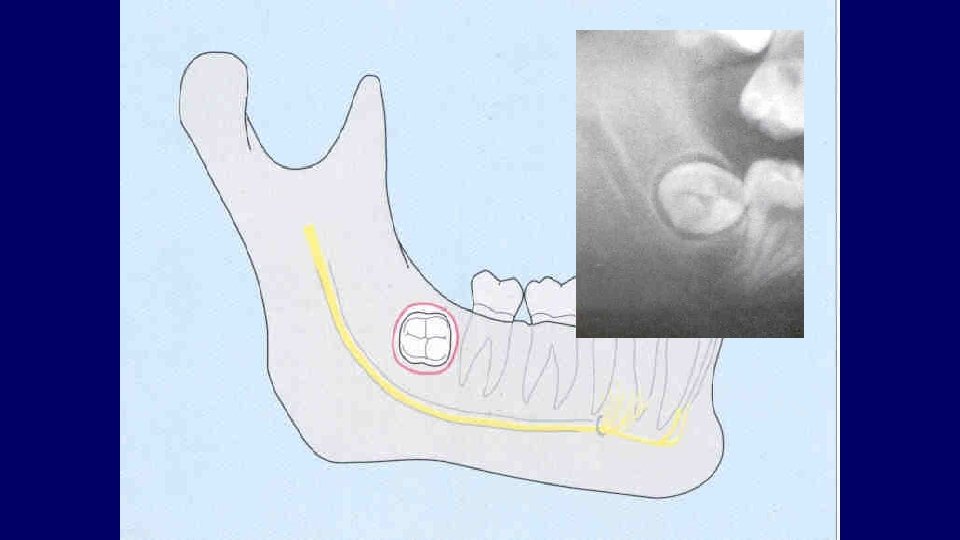

(2) Depth of impaction

Pell & Gregory Classification • Based on the amount of tooth covered by the anterior border of the ramus • The depth of the impaction relative to the adjacent tooth

Pell & Gregory • Relation to the Ramus Class III

Pell & Gregory • Depth of Impaction – Mandibular Class A Class B Class C

Pell & Gregory